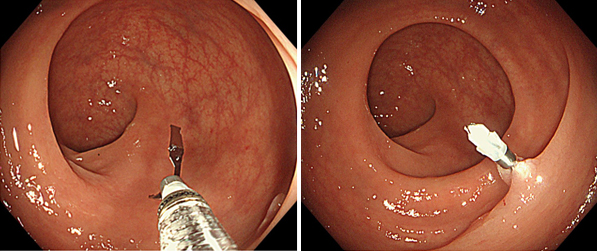

一般的には大腸カメラ検査と呼ばれている大腸内視鏡検査は、肛門から細長いスコープを入れて直腸から結腸、盲腸のほか、小腸の回腸末端までを直接観察できます。そのため微小な病変も見つけやすく、高精度な検査です。